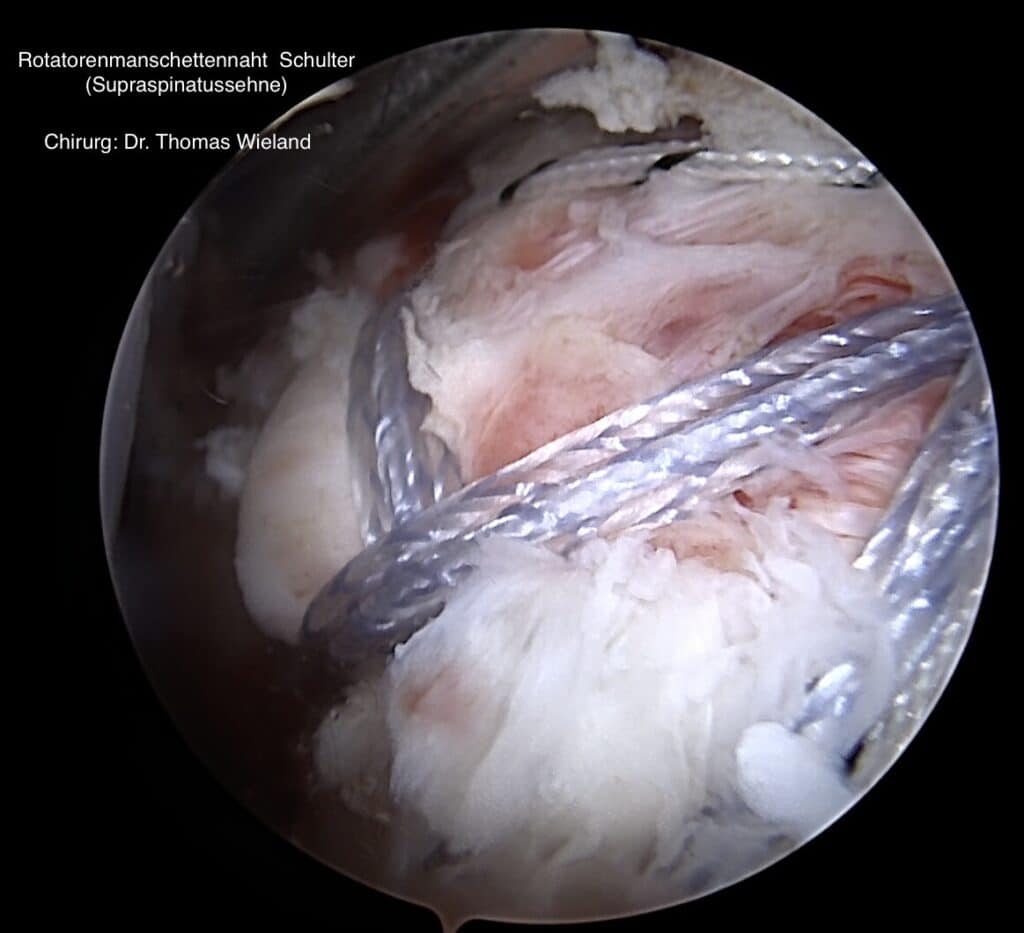

Die Rotatorenmanschette besteht aus 4 Muskeln mit ihren Sehnen, der Supraspinatus-, der Infraspinatus-, der Subscapularis– und der Teres minor Muskel. Dieser Muskel-Sehnenmantel legt sich wie eine Kapuze über den Oberarmkopf und kontrolliert so jede Drehung des Armes von der Schulter aus. Zusätzlich ist eine intakte Rotatorenmanschette für die Stabilität des Schultergelenkes sehr wichtig. Verletzungen an der Rotatorenmanschette (meist die Supraspinatussehne) sind sehr häufig, da die Rotatorenmanschette in der Schulter großen Belastungen unterliegt.

Verletzungsmuster an der Rotatorenmanschette (Supraspinatussehne, Infraspinatussehne, Subscapularissehne)

Werden kleine Läsionen festgestellt, so können diese zumeist unter fachkundiger Einzelheilgymnastik behandelt werden, denn das erste Ziel zur Behandlung von Schmerzen und Verletzungen an der Schulter ist stets die „Konservative Therapie“. Größere Risse im Bereich der Rotorenmanschette erfordern jedoch häufig eine chirurgische Sanierung.